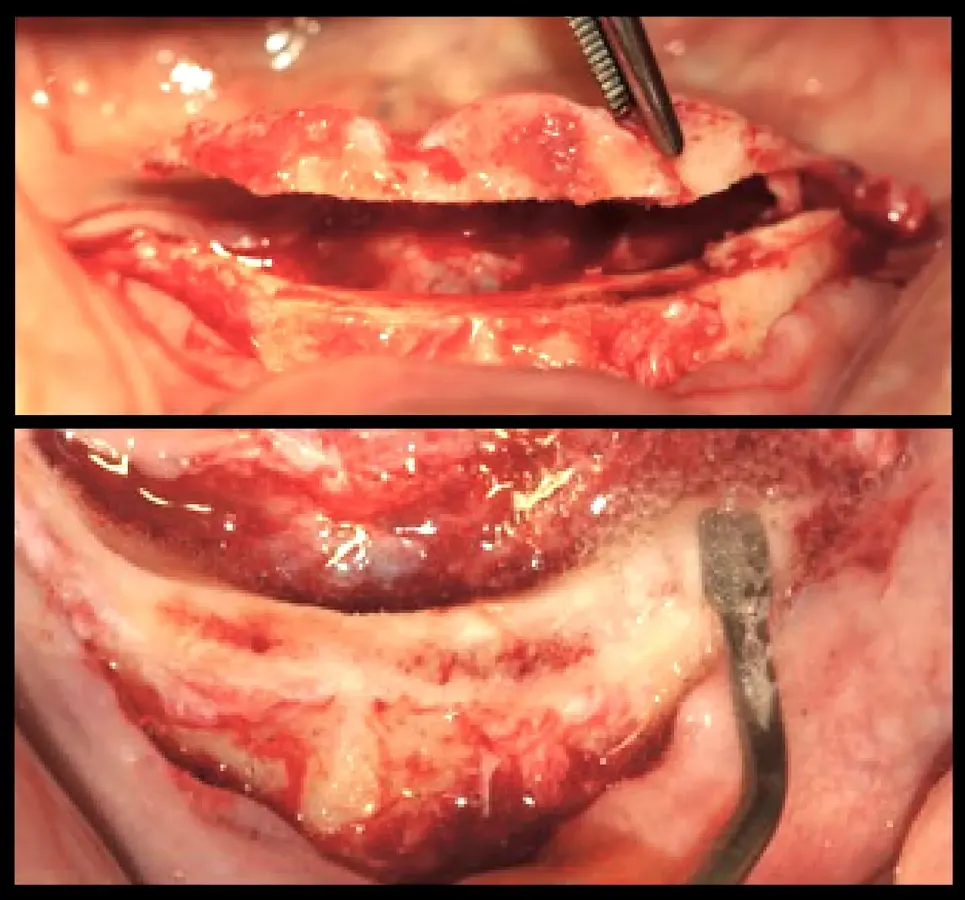

Paciente de ochenta y dos años de edad, de sexo masculino, acudió a la consulta odontológica refiriendo la necesidad de una prótesis inferior y malestar con la prótesis fija superior maxilar. El paciente refirió que le diagnosticaron diabetes mellitus tipo 2 hace 15 años. Refirió también haber tenido carcinoma de próstata y haber recibido radioterapia, hormonoterapia y orquiectomía. La última dosis de radioterapia la había recibido hace 72 meses y fue de 78 Gy en total. El paciente tenía un ASA2 según la clasificación del estado físico de la Sociedad Americana de Anestesiología (ASA)8,9. Asímismo, autorizó la recolección de la información y el uso de fotografías para su publicación con la firma de un consentimiento informado. En la evaluación intraoral, se observó coronas metal cerámicas tipo veneer en las piezas superiores con mala adaptación, acúmulo de placa bacteriana y edentulismo mandibular. Se inició el tratamiento con la motivación e instrucción de higiene oral, se procedió con la eliminación de las bolsas periodontales mediante raspado y alisado radicular. Estabilizada la salud periodontal, se realizó el alargamiento de las coronas clínicas. La gingivectomía se realizó con el electrobisturí (Servotome, Acteon), mientras que para el remodelado óseo se utilizaron los insertos P2LD del piezoeléctrico (Piezomed, W&H) (Figura 2).

Recontorneo gingival

Figura 2. Recontorneo gingival y alargamiento de corona clínica mínimamente invasiva mediante cirugía piezoeléctrica, donde se remodela el hueso sin elevar grandes colgajos (a). Se utilizaron los insertos de piezoeléctrico P2LD de W&H (b).

El procedimiento quirúrgico se inició con la asepsia y antisepsia del campo operatorio y del paciente. A continuación, se colocó anestesia infiltrativa a nivel de la proyección de salida de los agujeros mentonianos, se procedió con la incisión y decolado. Se realizó la delimitación y regularización del reborde óseo mediante el inserto aserrado B7 y el subsiguiente remodelado del reborde crestal mediante el inserto plano diamantado S1 del piezoeléctrico Piezomed (W&H) (Figuras 4 y 5).

Remodelado óseo

Figura 4. Remodelado óseo mínimamente traumático realizado con tecnología piezoeléctrica.